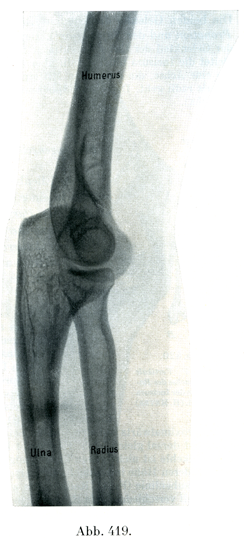

[図418, 419]肘関節27才の処女の腕のレントゲン像. 図418は掌側から背側へ照射,図419は尺側から橈側へ照射.